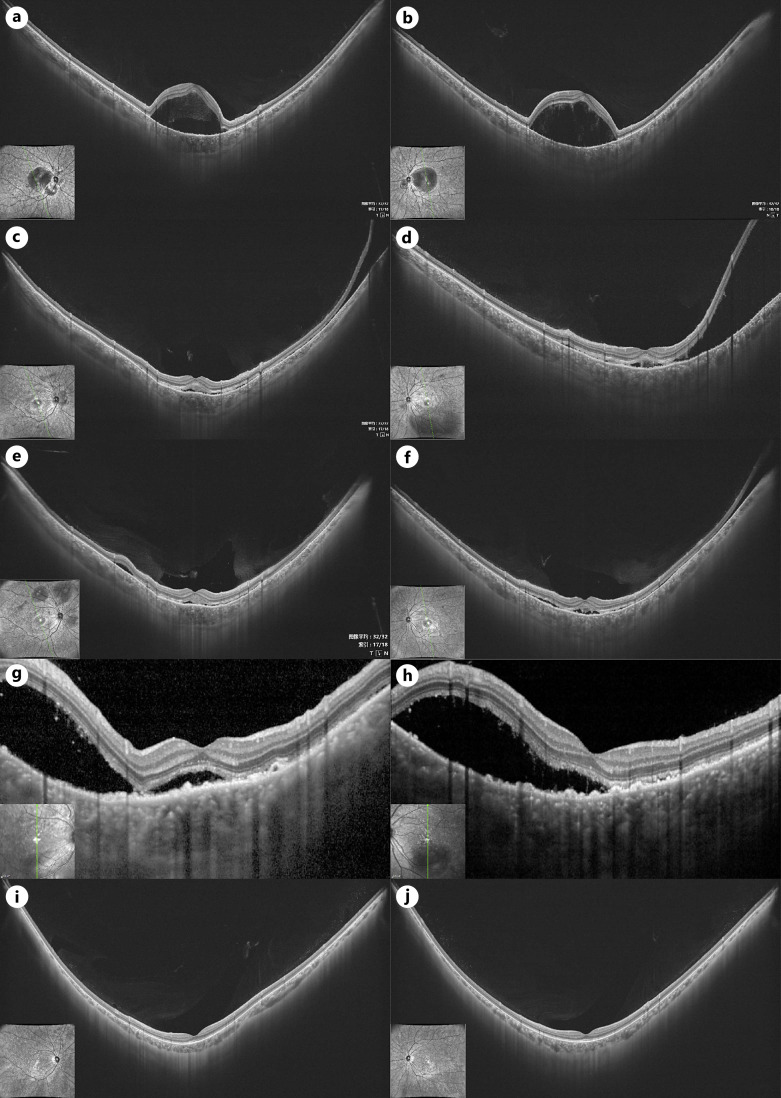

浆液性视网膜脱离(SRD)有多种病因,低白蛋白血症是其中一种罕见的病因。我们报告一例双侧SRD归因于血清白蛋白水平下降引起的系统性红斑狼疮(SLE)。病例介绍:28岁女性,无明显既往病史,双侧眼睑水肿10天,视力模糊3天。光学相干断层扫描显示双眼视网膜下积液;荧光素血管造影显示多个高荧光斑点,伴晚期渗漏和池化。广泛的血清学和全身检查显示血清白蛋白水平轻微下降,无其他明显异常。由于怀疑诊断为Vogt-Koyanagi-Harada病,患者接受了大剂量静脉注射皮质类固醇治疗,但没有任何改善。然而,在白蛋白补充和皮质类固醇剂量逐渐减少后,取得了显著的临床改善。该患者的白蛋白水平下降最终被发现是由于SLE引起的蛋白质丢失性肠病(PLE)。结论:该病例是一种罕见的双侧SRD伴slee相关PLE所致低白蛋白血症的病例。报告显示,眼部受累,如眼睑水肿和SRD可能是SLE的初始表现,而不是常见的狼疮视网膜病变。它强调了眼部表现作为及时诊断和处理系统性疾病的线索的价值。

Case presentation: A 28-year-old female with no significant past medical history presented with bilateral palpebral edema for 10 days and blurred vision for 3 days. Optical coherence tomography demonstrated subretinal fluid in both eyes; fluorescein angiography revealed multiple hyperfluorescent spots with late leakage and pooling. Extensive serological and systemic examinations showed a slight decrease in serum albumin level with no other notable abnormalities. With the suspected diagnosis of Vogt-Koyanagi-Harada disease, the patient received high-dose intravenous corticosteroid therapy without any improvement. However, significant clinical improvement was achieved after albumin supplementation and corticosteroid dose tapering. The decrease in albumin levels in this patient was ultimately found to be due to protein-losing enteropathy (PLE) caused by SLE.